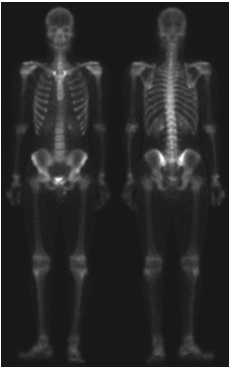

위의 사진은 뼈 감염이나 종양 같은 질환은 감지하는 전신 골격 원자력 스캔입니다. 디지털 영상 처리는 문제 지향형이기 때문에 어떤 문제를 가지느냐에 따라서 서로 다른 방향성을 가지게 됩니다. 저희는 사진에 있는 골격의 디테일을 살리는 것으로 하겠습니다. 지난 포스팅에서 따로 설명은 드리지 않았지만 라플라시안 필터는 영상의 세세한 디테일을 살리는 데 사용될 수 있으며 그래디언트 기반 필터링은 영상 내의 중요한 엣지를 찾아내는 데 도움을 줄 수 있습니다.

입력 영상 $I$에 라플라시안 필터를 적용하는 것은 라플라시안 필터를 이용한 영상 샤프닝의 시작이라고 하였습니다. 하지만 위의 그림을 보면 영상 내의 노이즈가 꽤 많이 있기 때문에 샤프닝된 영상은 노이즈가 많을 것이라고 예상할 수 있습니다.